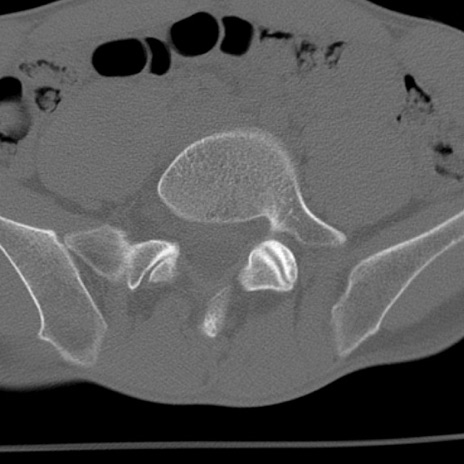

症例3 腰椎CT(横断像)

腰椎CT